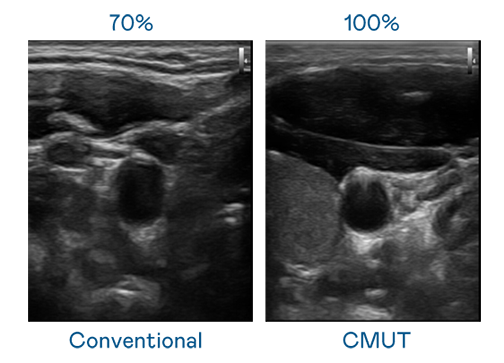

CMUT 技术是一种用电容式微机电元件来产生超音波讯号的技术。与传统 PZT 压电式技术相比,CMUT 频宽增加 30%,更宽频的超音波讯号让影像解析度大幅提升,是实现高影像品质医疗超音波扫描、促进精准医疗发展的关键技术。

大频宽带来超清晰影像

超音波影像的解析度高低,首先取决于探头能发出的讯号频宽。PT视讯 CMUT 可提供高清晰的超音波讯号,提供高频宽、高灵敏度、影像纹理细节更高的超音波影像,协助医护人员缩短影像判读时间及利用精准的医疗影像进行诊断。